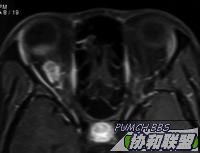

患者女性30岁。主诉右眼视力下降半年。检查右眼视力眼前手动,眼前节正常。眼底见后极部颞侧实性隆起,周边浅层网脱。超声及MRI见图。全身检查未发现明显异常。

增强

图片点击可在新窗口打开查看